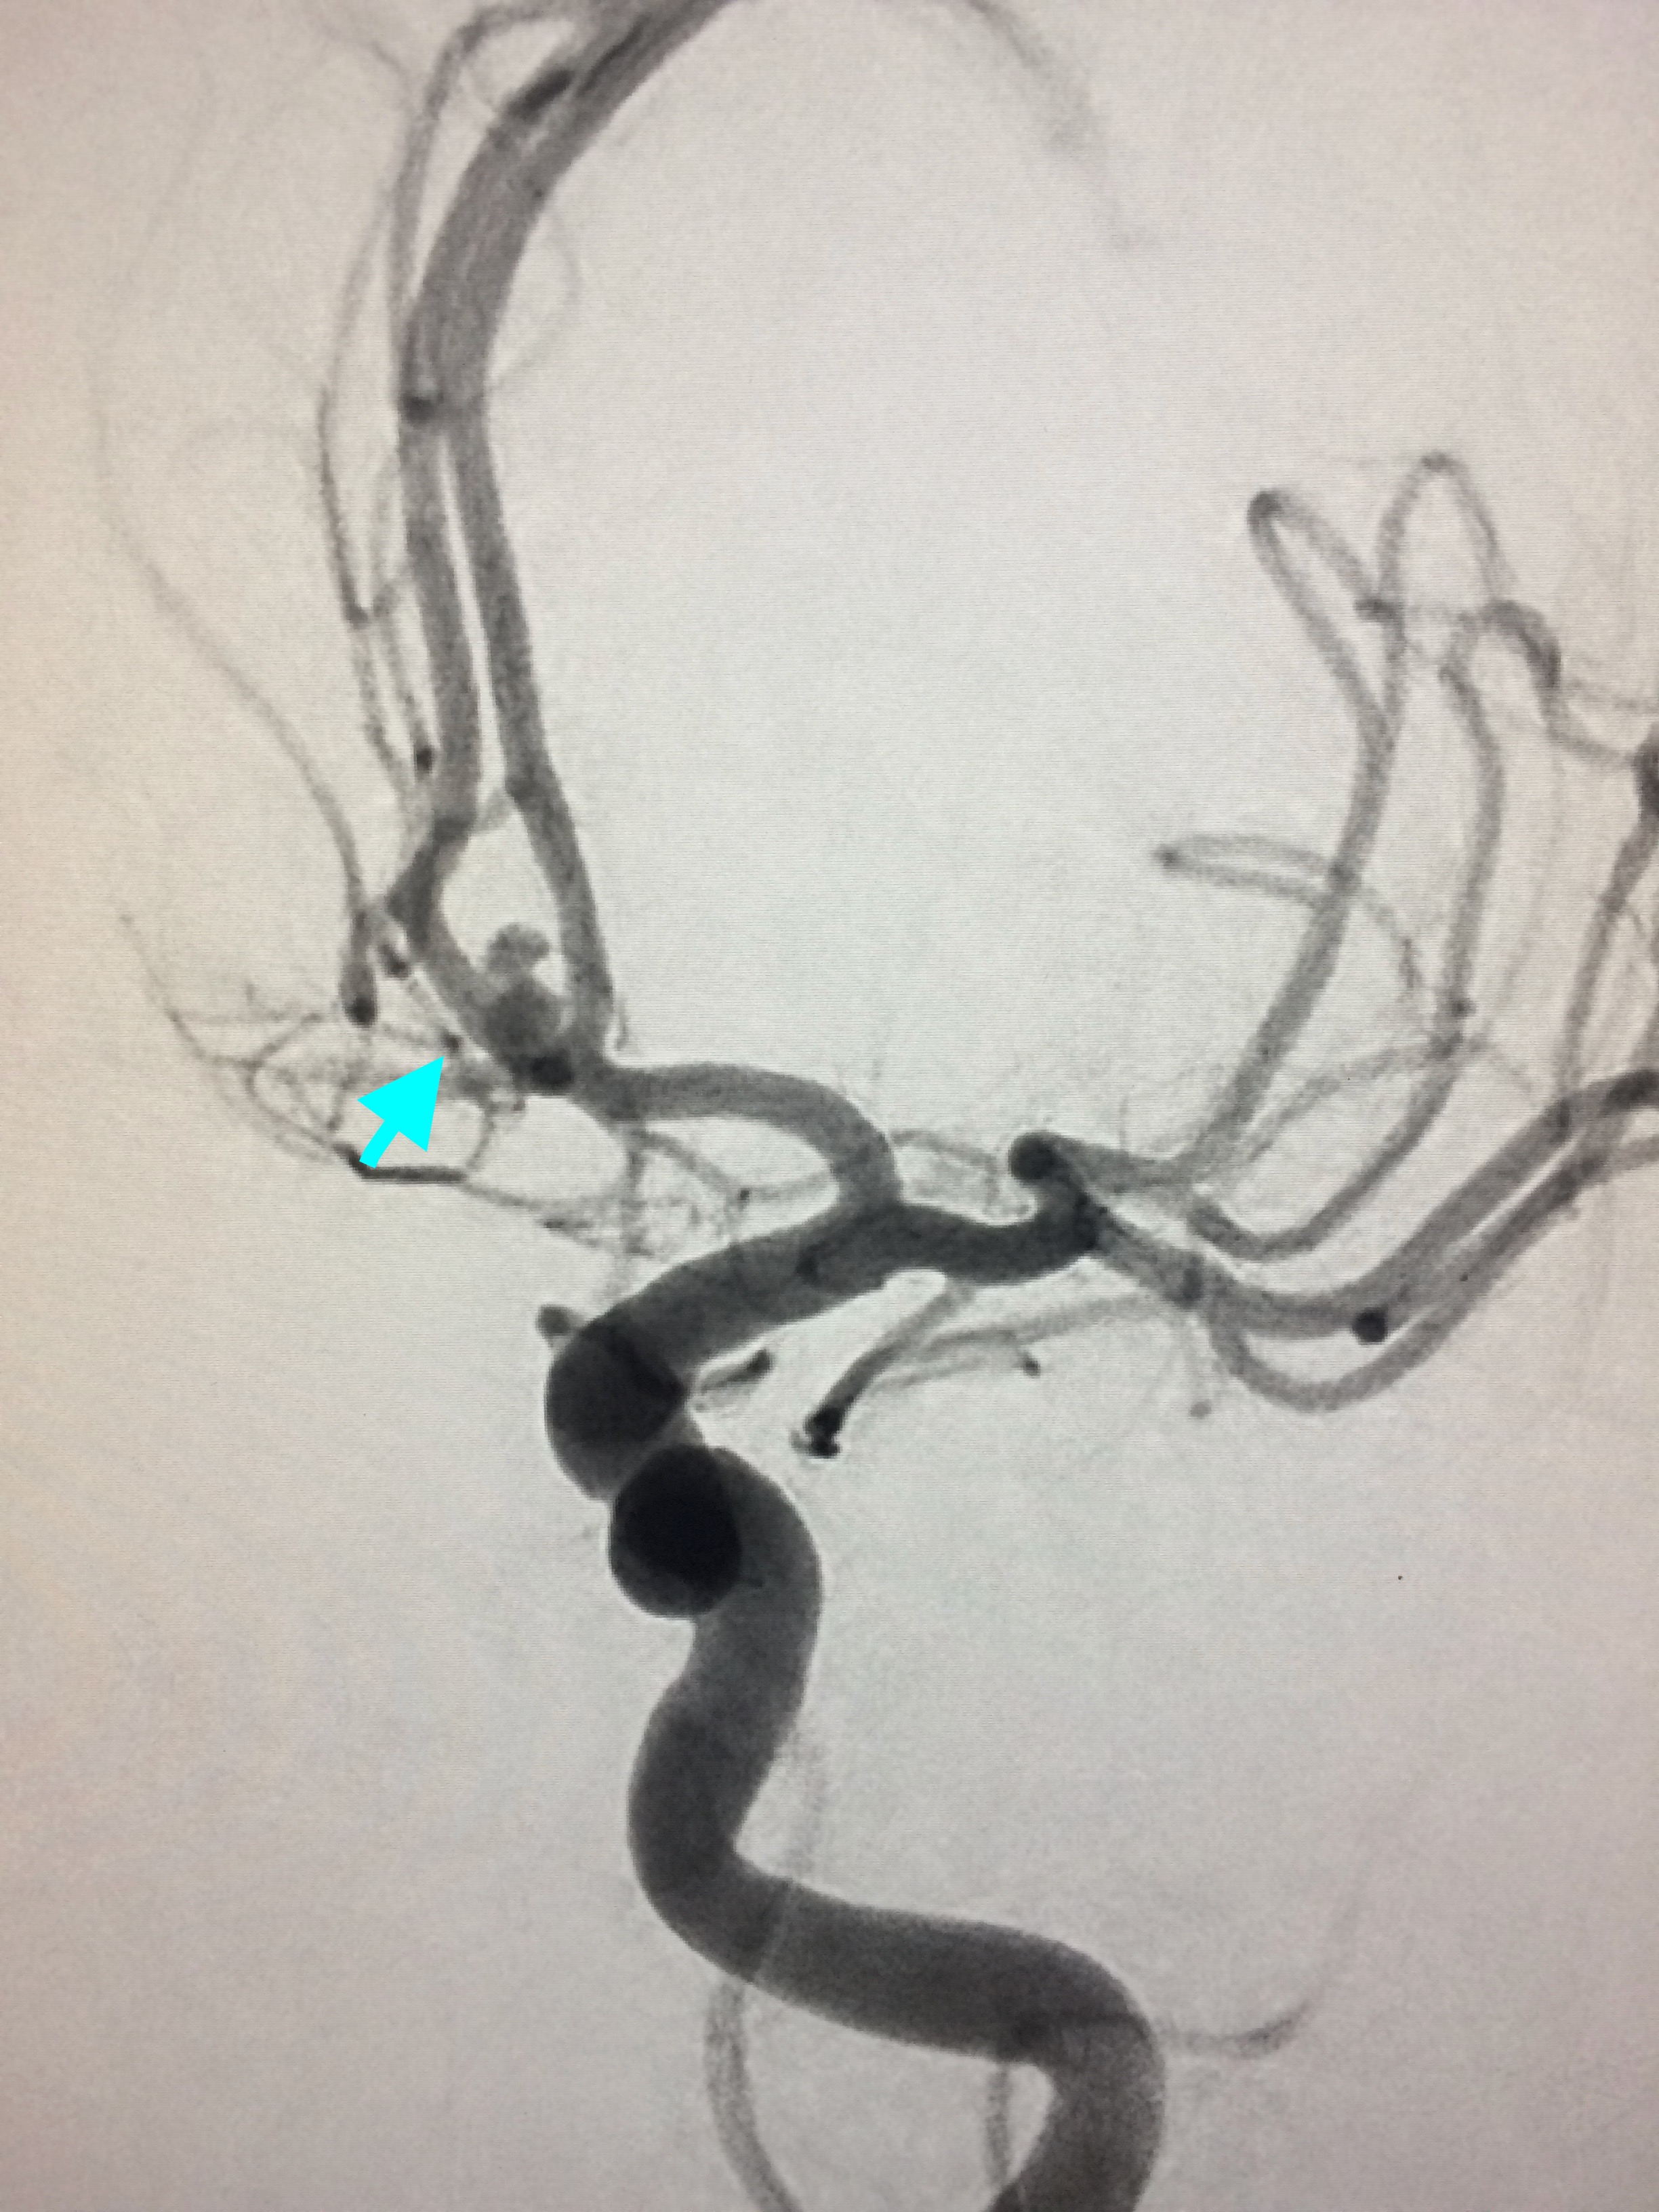

The Myth That Small Brain Aneurysms Don’t Rupture